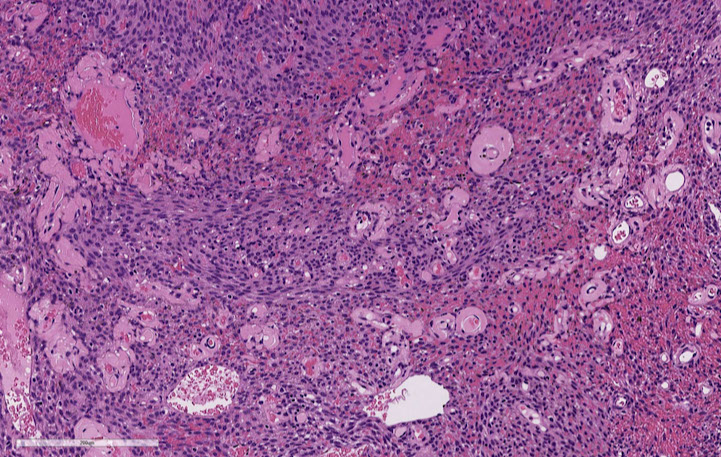

Nasopharyngeal ca

Nasopharyngeal ca - EBER

Nasoparyneal Carcinoma

- subtypes: keratinizing (1/4), nonkeratinizing (1/7) or undifferentiated (3/5)

- ~1/5 cancers in China

- inc EBV titers in non-K and undiff types, no clear causal relation

- different growth patterns: Rigaud (cohesive) vs Schminke (discohesive)

Keratizing: looks like any other SCC

Nonkeratinizing (undifferentiating) subtype

- common in SE Asia and parts of Asia, younger pts usually; sometimes presenting as a neck mass

- no K, syncytial groups of large cells c pale chromatin and mprominent nucleoli, inc lymphs, no desmoplasia

- genetic and envt factors (1/5 cancers in Hong Kong), assoc c A2/sin HLA profile in chinese

- EBV assoc

- asymptomatic; neck mass

Tx: Rads (high dose) usually done 2/2 stage

- K type not responsive to rads

Px: undifferentiated has the best px (radiosensitive)